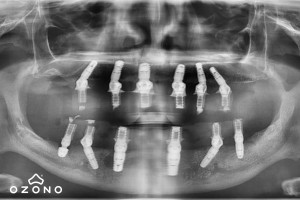

Sistemul de implanturi dentare cu încărcare (protezare) imediată All-On-4/All-On-6 oferă pacienților ocupați o soluție de tratament ce presupune restaurarea rapidă și completă a arcadei superioare sau inferioare, pentru ca aceștia să își poată relua viața socială chiar a doua zi.Ce presupune această intervenție? Inserarea a 6 implanturi dentare la maxilarul superior (deoarece maxilarul are o densitate osoasă scăzută) și 4 implanturi dentare la mandibulă (maxilarul inferior).

La 6-12 luni după inserarea implanturilor dentare pacientul trebuie să revină în clinică pentru aplicarea lucrării dentare definitive.Cu ce se diferențiază All-On-4/All-On-6 de sistemul clasic de implant dentar?

Sistemul clasic este recomandat pentru un implant dentar sau mai multe aflate în zonele care nu sunt vizibile și presupune aplicarea lucrării definitive după o perioadă de 4-6 luni. Acesta este cel mai mare dezavantaj pentru pacienții care doresc o soluție rapidă de recăpătare a zâmbetului.Pe de altă parte, sistemul All-On-4/All-On-6 este indicat pacienților care nu mai au dinți naturali pe arcadă sau dacă aceștia există, sunt foarte bolnavi și vor fi extrași în cadrul intervenției de aplicare a implanturilor precum și situațiilor în care pacientul este deja purtător de proteză mobilă dar nu o poate suporta.